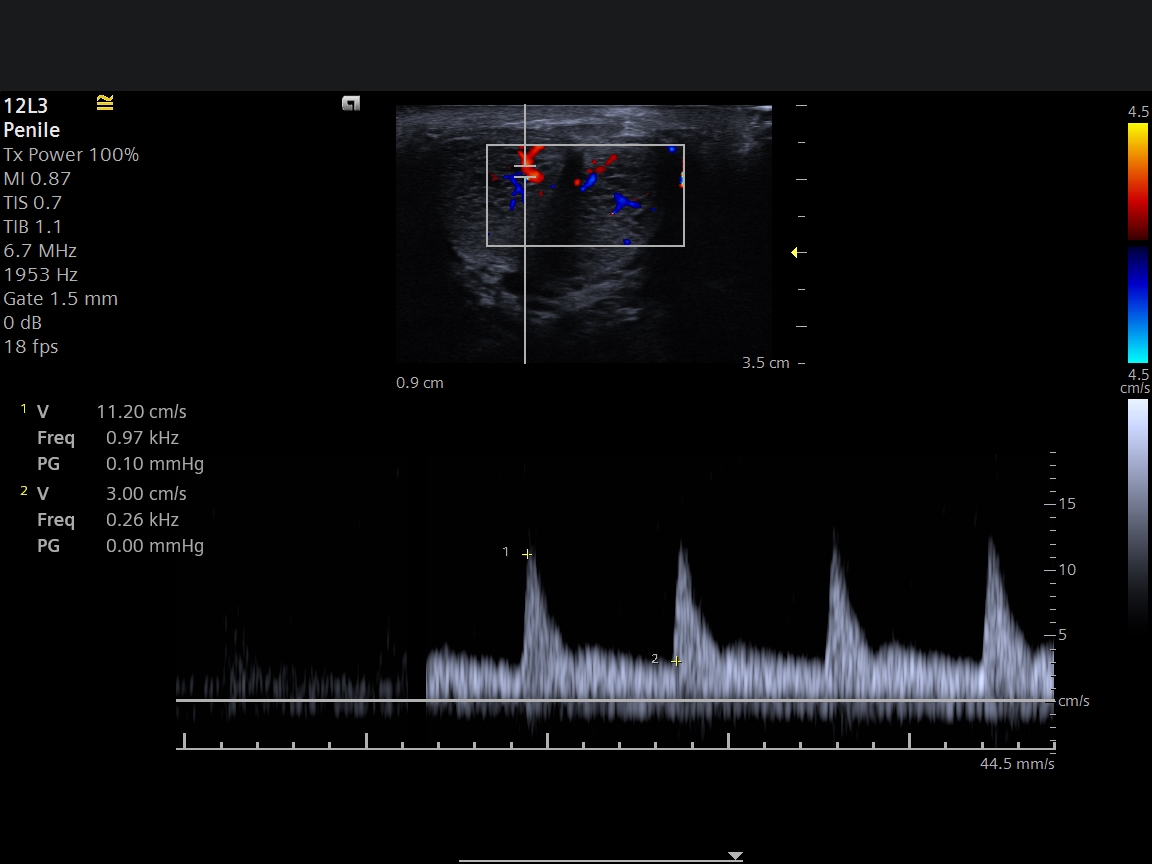

Penil Doppler Ultrasonografi Nedir?